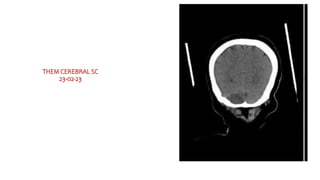

THEM CEREBRAL SC

23-02-23